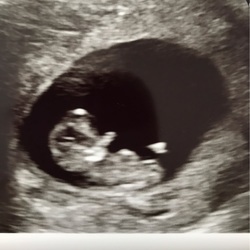

Helaas zojuist bruin bloedverlies, dus ben heel bang dat de gezonde vrucht ook nu aan het afstoten is ondanks dat hier in principe geen aanleiding voor zou moeten zijn. Ja, de velen medicatie en de shocks op mijn lichaam 24 uur lang